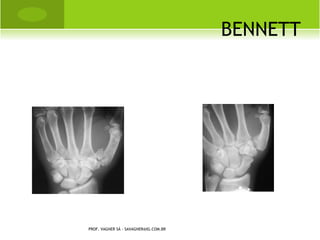

B ENNETT